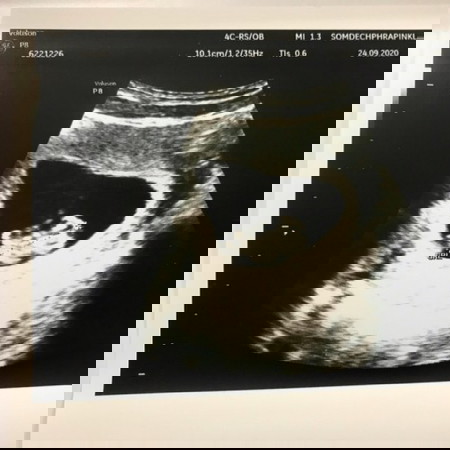

อัลตร้าซาวครั้งเเรกในชีวิต ตื่นเต้นมากคะ

น้องกำลังได้ 9 w คะ